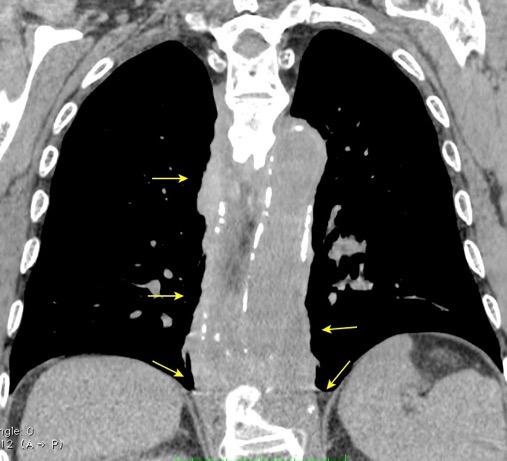

T. mixto de células

Ganglios retroperitoneales (flechas negras)

germinales del testículo izquierdo Nódulos pulmonares múltiples. (flechas verdes). Ganglios paratraqueales. (flechas amarillas). Dudoso ensanchamiento retrocrural (flechas negras)

Panda A et al. “Straddling Across Boundaries”. Thoracoabdominal Lesions: Spectrum and Pattern Approach. Curr Probl Diagn Radiol, 2015